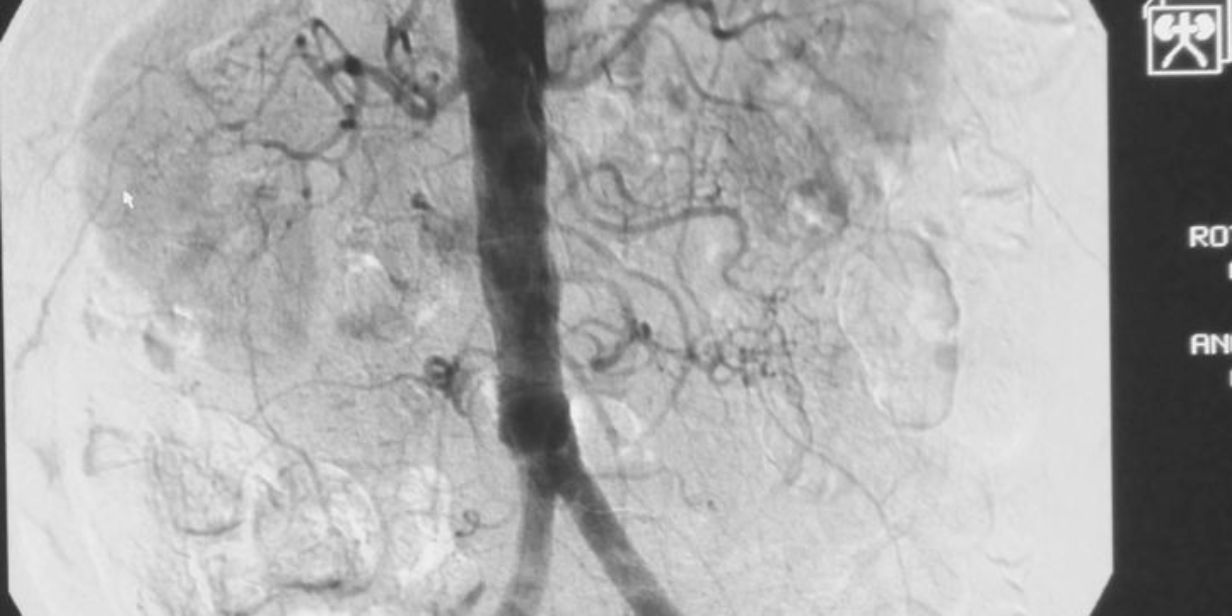

L'angiotermografia dinamica nasce più tardi, come evoluzione della termografia a contatto o termografia mammaria, facendo uso sempre di cristalli liquidi, ma con un rivelatore migliorato e in una concezione diversa. La differenza sta nell'identificare, piuttosto che il calore generato dal tumore, il calore dovuto alla vascolarizzazione della ghiandola mammaria. Il principio su cui ci si basa è che un tumore per nascere, svilupparsi e crescere ha bisogno di un forte afflusso di sangue (teoria dell'angiogenesi) e quindi l'immagine acquisita conterrà informazioni relative ad una modificata vascolarizzazione in presenza di un tumore. L'idea di base è che ogni donna ha la propria immagine termografica, che è come un'impronta digitale, e che l'alterazione di questa immagine è prova di una sospetta attività tumorale o pretumorale. L'importanza dell'influenza delle neoplasie nella vascolarizzazione fu evidenziata e studiata approfonditamente da Judah Folkman nelle sue ricerche sull'angiogenesi a partire dal 1965 e gli valse il Premio Wolf per la medicina nel 1992. Basandosi, quindi, su questa teoria, l'angiotermografia dinamica studia la vascolarizzazione ed è in grado di visualizzare tumori anche in stato precanceroso, la cui rimozione rimuove la causa del tumore.

La macchina con la quale si effettua questo esame è composta da due parti: la prima, mobile, è composta dal sensore termografico da appoggiare sulla mammella, la seconda è formata dalla base collegata ad un computer che ha il compito di registrare le immagini acquisite. Il sensore è una placca a cristalli liquidi, migliorato sia in sensibilità che in risoluzione spaziale, che registra la distribuzione del sangue a temperature tra 30° e 35°. Quando il sensore è appoggiato alla mammella il calore dovuto alla vascolarizzazione eccita gli atomi del cristallo che cambiano colore. Mentre nella termografia a contatto precedente il medico studiava il colore, nella nuova metodologia angiotermografica il medico studia la forma dell'immagine che si crea. In una mammella sana l'immagine formatasi è dovuta alla normale vascolarizzazione che si presenta come vari segni che risultano essere a punta in direzione del capezzolo. Nel caso di un tumore o anche di una lesione precancerosa compaiono segni che hanno forme arrotondate o che convergono da zone diverse della mammella per 'nutrire' il tumore. Quindi l'interpretazione dell'immagine si basa sulla morfologia. La procedura standard prevede che si esamini prima la paziente clinicamente (visita con palpazione) e poi che si acquisiscano due proiezioni della mammella destra (laterale e frontale) e due della sinistra (laterale e frontale). Si scattano le foto digitali ed eventualmente si confrontano i risultati con altre foto termografiche acquisite in precedenza. Nel caso in cui ci siano evidenti vene superficiali si raffredda la mammella con uno strumento simile a un fon.